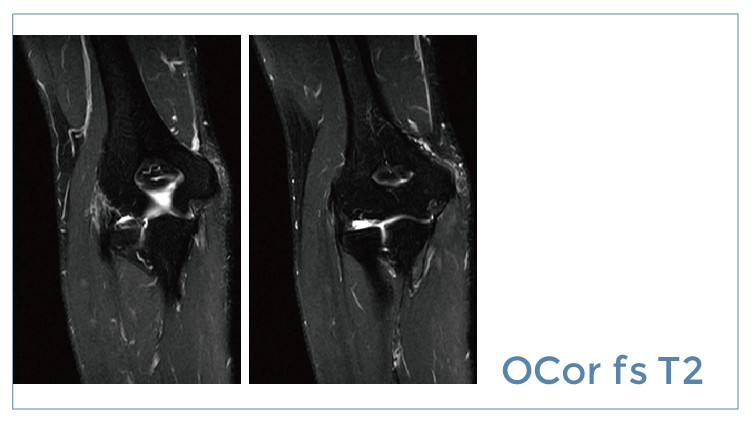

【朗润影像档案】20190726磁共振影像病例结果讨论